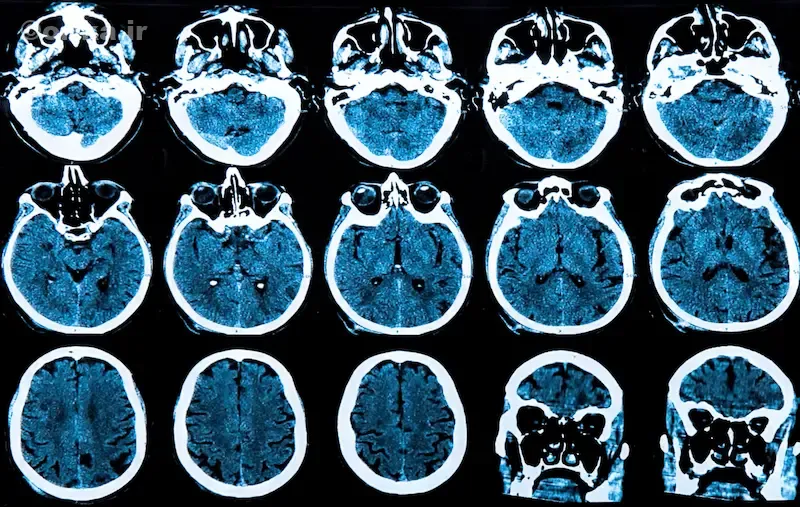

تخریب عصبی در مراحل اولیه از استریاتوم آغاز میشود؛ ناحیهای که در کنترل حرکت و احساس پاداش نقش دارد. در پی تحلیل تدریجی سلولهای این بخش، حرکات بدن از کنترل خارج میشوند. MRI نشاندهنده آتروفی هسته دمدار (Caudate nucleus) و بزرگشدن بطنهای جانبی است.

پزشک متخصص مغز و اعصاب معمولاً از MRI و گاهی PET-scan برای بررسی آتروفی مغز استفاده میکند. در مراحل اولیه، تغییرات تصویری شامل باریکشدن استریاتوم و افزایش فضاهای بطنی است. مهم است که بیماریهای مشابه مانند HDL2، SCA17، Wilson و parkinsonism از هانتینگتون افتراق داده شوند. قطعیت تشخیص، فقط با تست ژنتیک مستقیم HTT CAG ممکن است.